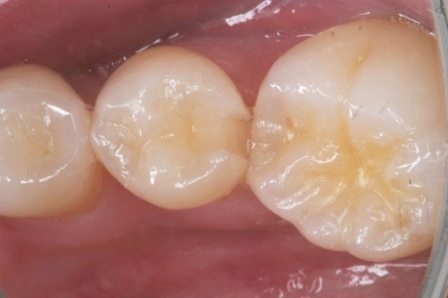

下顎7番の頬側歯茎部カリエスの原因 2025.06.04